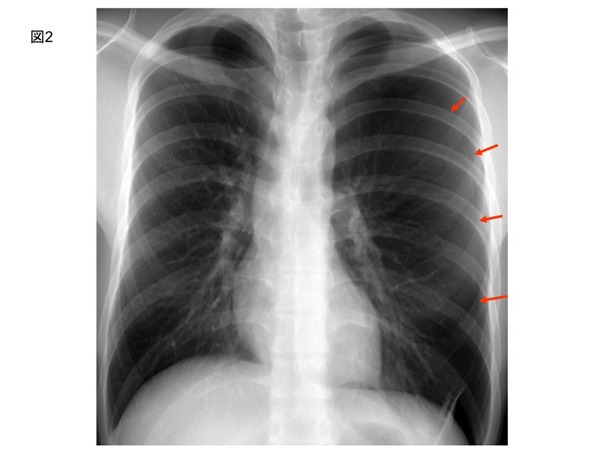

また、呼吸性にQRS電位の変動がみられる。図2にこの症例の胸部レントゲン写真を示す。

矢印で示すように左の気胸がみられる。

胸部レントゲン写真